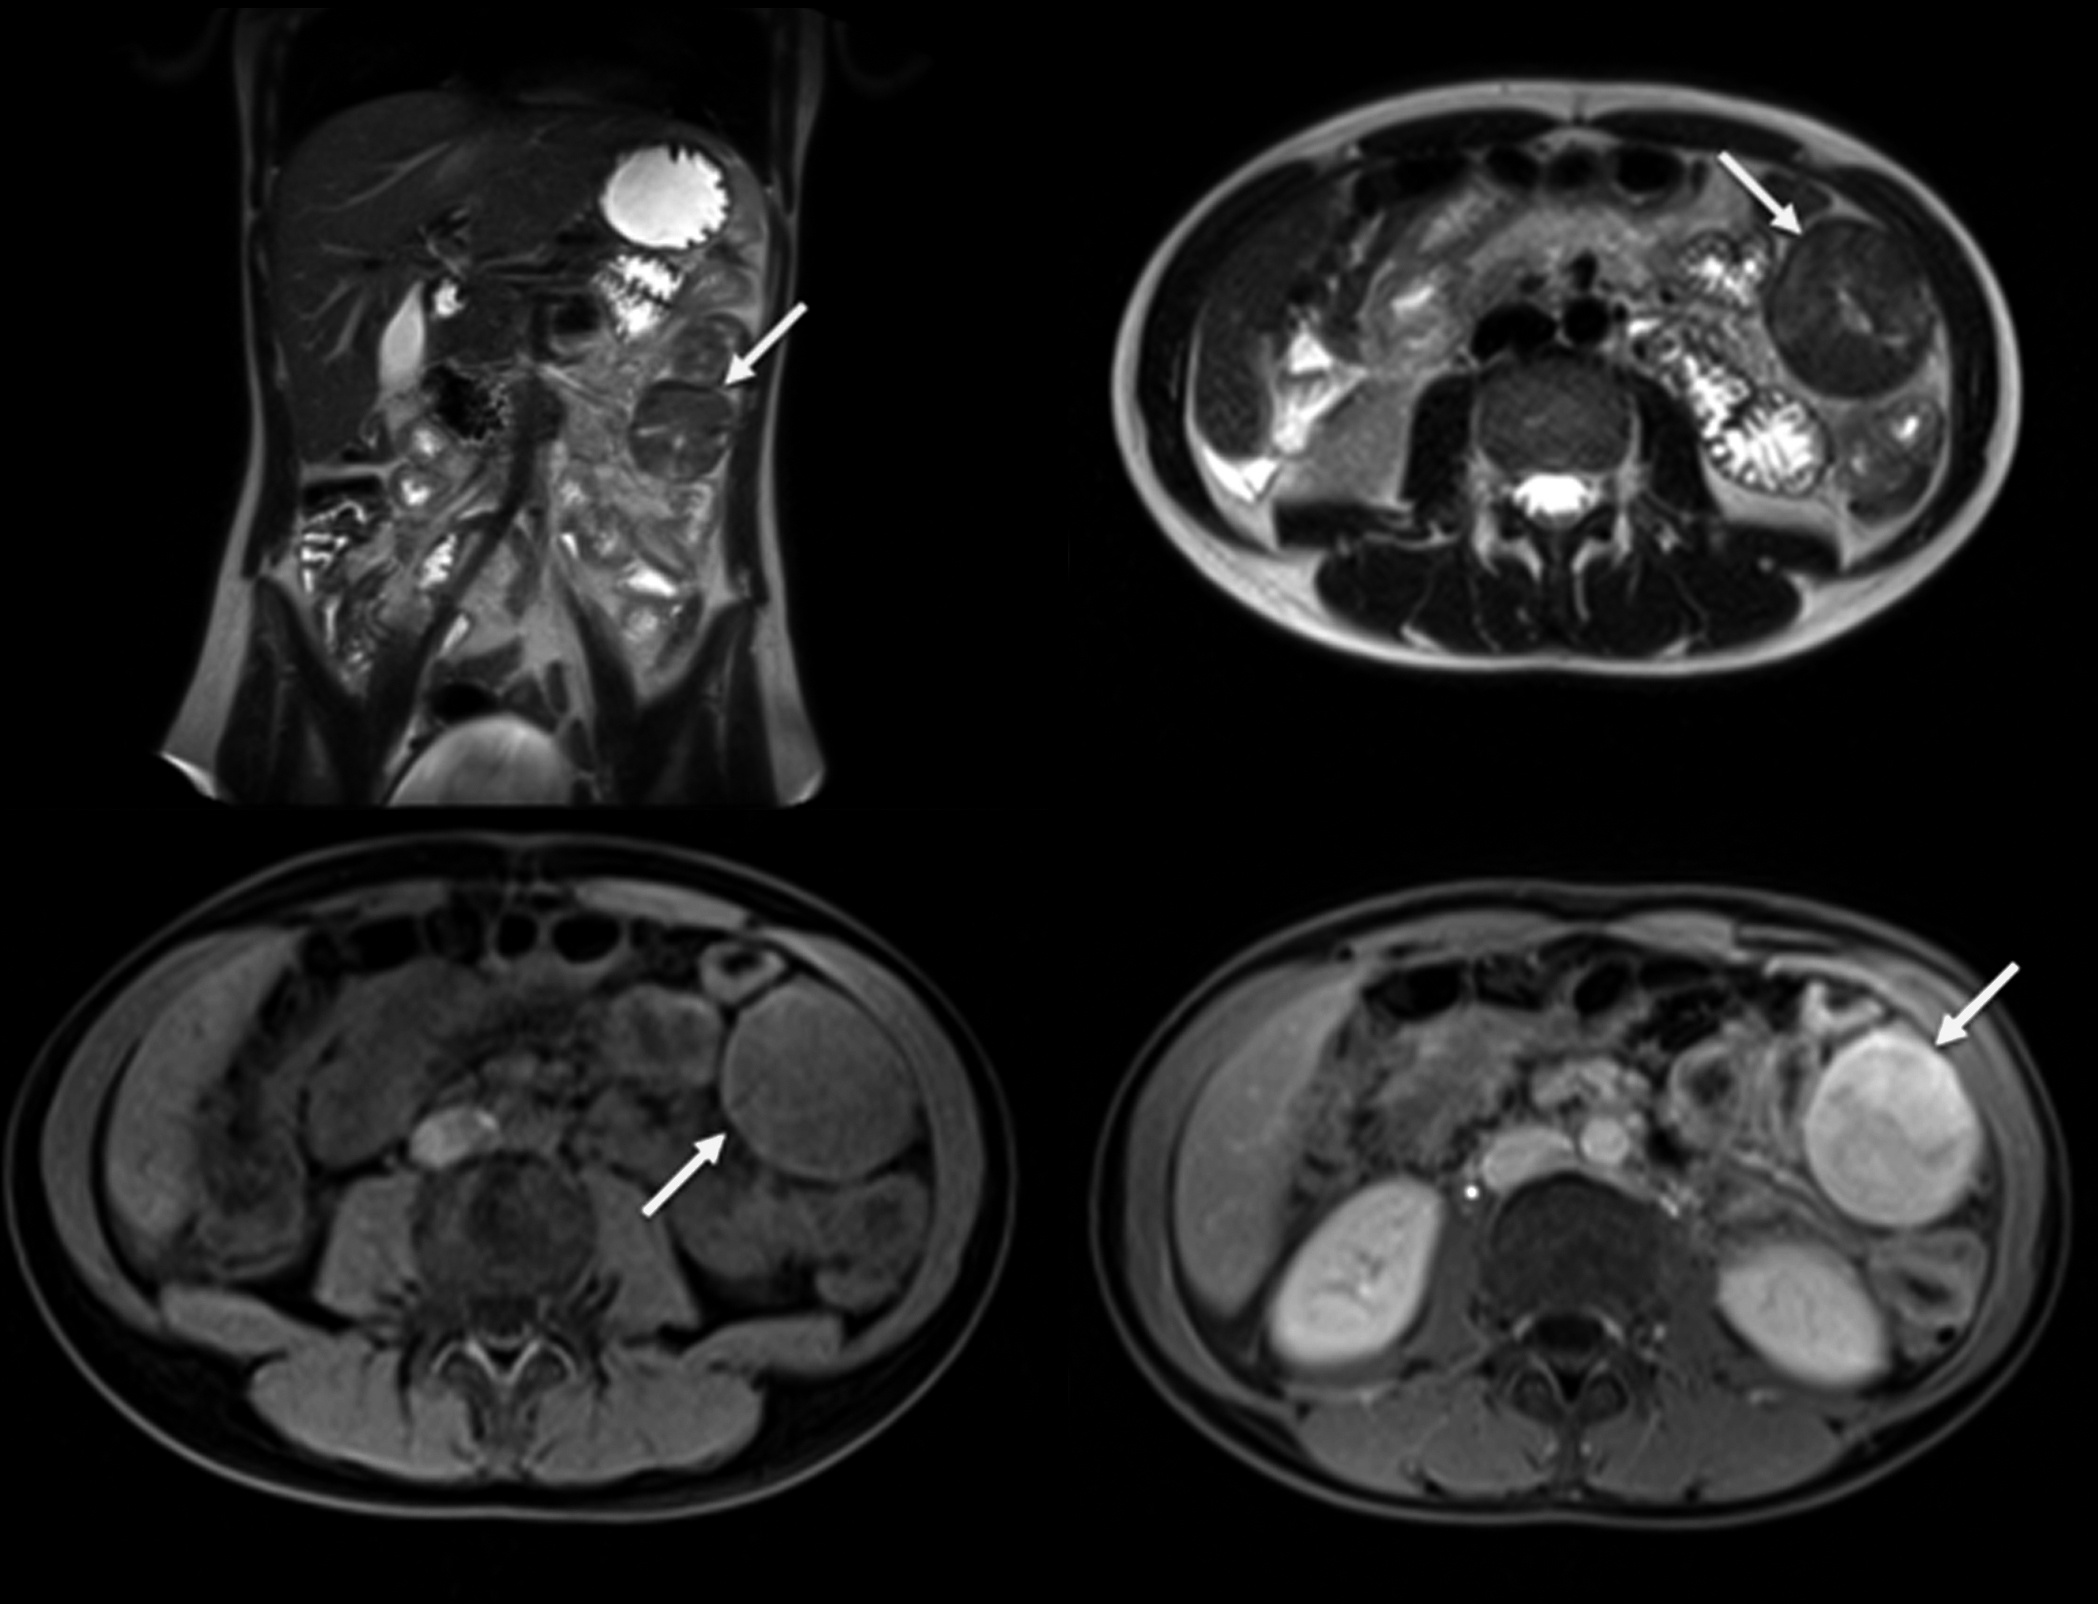

Se solicita RM, que se realiza en condiciones basales y tras la administración de gadolinio. Se observa tumoración sólida de igual tamaño y características que en TC previas, que impresiona de origen mesentérica o peritoneal y cambia de posición en estudios sucesivos, actualmente localizándose en flanco izquierdo. (Figura 8)

Figura 8

RM de abdomen: secuencia T2 coronal (a); secuencia T2 axial (b); secuencia ponderada en T1 axial (c); secuencia ponderada en T1 axial con contraste (d). Masa sólida del mismo tamaño y características que en las TC anteriores (flechas).

La apariencia de TC del TIM abdominal es variable. La masa puede ser hipo o isodensa en relación al músculo en exploraciones sin contraste y se han observado calcificaciones en casos en páncreas, estómago e hígado. Tras la administración de medio de contraste generalmente hay realce pero no es muy pronunciado. Se han observado variedad de patrones que incluyen desde la ausencia de realce, realce periférico temprano con relleno central tardío, realce heterogéneo y realce homogéneo. Las lesiones más grandes pueden tener necrosis central (1, 4, 12, 14, 15). En las imágenes de RM, la apariencia de estos tumores también es variable. Generalmente son hipointensos en relación al músculo en imágenes potenciadas en T1, hiperintensas en imágenes potenciadas en T2 y con realce heterogéneo después de la administración de medio de contraste. (1, 4, 12, 15)